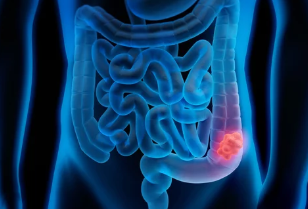

건강검진이나 대장내시경을 통해 "선종"과 "용종"이라는 용어를 들어본 적이 있을 겁니다. 이 둘은 모두 대장 건강에 중요한 관련이 있지만, 그 차이를 명확히 이해하는 것이 예방과 관리에 큰 도움이 됩니다. 이번 글에서는 선종과 용종의 차이, 발생 원인, 증상, 진단 및 관리 방법 등을 폭넓게 알아보겠습니다.

선종과 용종은 대장이나 소화기관에서 나타날 수 있는 조직의 비정상적인 성장을 뜻합니다. 하지만 이 둘은 성질과 향후 건강에 미치는 영향에서 차이가 있습니다.

- 선종: 용종의 한 종류로, 암으로 진행될 가능성이 있는 전암성 병변입니다. 선종이 발견되면 제거를 통해 대장암의 발생 위험을 낮출 수 있습니다.